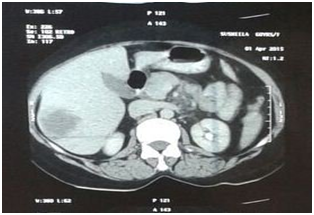

We report a case of 62 years female menopausal for 17 years operated for endometrial adenocarcinoma grade II (moderately differentiated). She underwent total abdominal hysterectomy & bilateral salpingoopherectomy. Then she received 35 cycles of brachytherapy. One year later she consulted for a cutaneous mass measuring 4x4cm, firm too hard, fixed at anterior left shoulder. FNAC was performed along with Liquid based cytology. Smears examined were cellular comprising neoplastic cells arranged in groups, sheets, acinar structures and dispersed singly having round to oval, moderately pleomorphic nuclei coarse nuclear chromatin, prominent nucleoli and moderately abundant cytoplasm which is vacuolated at places. Keeping in view previous histopathological diagnosis of endometrioid adenocarcinoma diagnosis of metastasis possibly from endometrial adenocarcinoma was made. Liquid based cytology also reveals groups, clusters & acini of these neoplastic cells in a relatively clean background. Immunocytochemistry (ICC) for Progesterone Receptor (PR) was negative on LBC smears suggesting poor prognosis. Then patient was further investigated and Ultrasonography (USG) abdomen, Contrast enhanced chest tomography (CECT) chest, abdomen & pelvis & haematological tests were performed. USG show hypoechoiclesion with areas of cavitation right lobe revealing metastasis. CECT show multiple heterogeneously enhancing hypodense lesion in right lobe of liver (metastasis), mediastinal & retroperitoneal lymphadenopathy, metastasis right lobe of lung & enhancing mass pre & paraaortic region. Based on FNAC report and clinical investigatory correlation patient was started with chemotherapy & radiotherapy (Figures 1-5).

Figure 2 CT revealing metastasis liver.